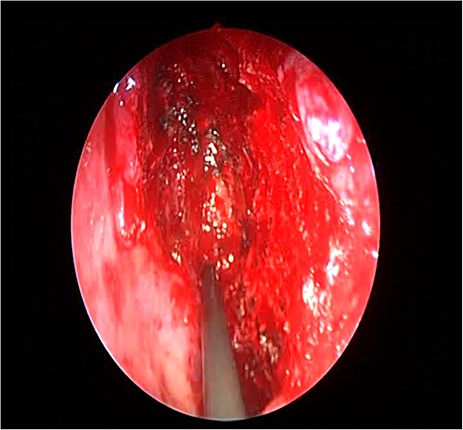

The patient underwent image-guided endoscopic endo-nasal removal (Fig. 5) of a large fibro-osseous tumor, the tumor was adherent to the orbit and skull base which was removed (Fig. 6). The resected tumor was sent to the histopathological examination, which confirmed the final diagnosis of fibrous dysplasia. The patient remained free of symptoms with no recurrence for 3 years after the resection.

Image-guided endoscopic tumor removal from orbit and skull base.